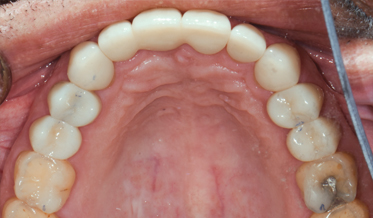

Adapting the Digital Reference Denture Technique for Full-Arch Cases Using a Novel Fixed Attachment System

Digital Workflow as an Aid to Complex Multidiscipline Dental Treatment for Improved Esthetics

Fred A. Puccio, DDS; and Gregori M. Kurtzman, DDS